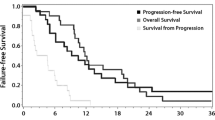

The Receiver Operating Characteristic (ROC) curves can be found in Fig. 2; in both curves TP was seen as the positive state. The VOI-based analysis showed an AUROC of 0.72 (95%-CI: 0.58–0.86) and 0.82 (95%-CI: 0.70–0.94) for rCBVmax values and rCBVmean values, respectively. Regarding rCBVmax, a cut-off value of 5.1 mL/100 g resulted in a sensitivity of 69% and specificity of 67%. A cut-off value of the rCBVmean of 1.11 mL/100 g resulted in a balanced sensitivity and specificity value of 72% and 76%, respectively, to distinguish TP from TRA.

Receiver operator characteristics (ROC) curves based on the ‘hot spot’ (A) and semi-automatic volume of interest (B) analysis of relative cerebral blood volume (rCBV) data to distinguish tumor progression from treatment related abnormalities. Area under the ROC curve (AUROC) for the rCBV ratio of the ‘hot spot’ analysis was 0.69 (95%-CI: 0.61–0.78). The AUROC of rCBVmax and rCBVmean are 0.72 (95%-CI: 0.58–0.86) and 0.82 (95%-CI: 0.70–0.94) respectively

For the semi-quantitative ‘hot spot’ analysis an ROC curve based on measured rCBV ratio was made based on the combined analysis of the three readers. This resulted in an AUROC of 0.69 (95%-CI: 0.61–0.78). The achieved sensitivity and specificity of this analysis is 67% and 70%, based on a balanced rCBV cut-off of 1.63 mL/100 g. DeLong’s test used on the semi-automatic VOI analysis ROC curve indicated a significant difference between the AUROC of the rCBVmean and rCBV ratio from the ‘hot spot’ analysis (Z = -2.26, p = 0.023). It also showed a significant difference between the AUROC of rCBVmean and rCBVmax (Z = -2.655, p = 0.0079) and a non-significant difference between the AUROC of the rCBVmax and the rCBV ratio from the ‘hot spot’ analysis (Z = -0.50, p = 0.61).